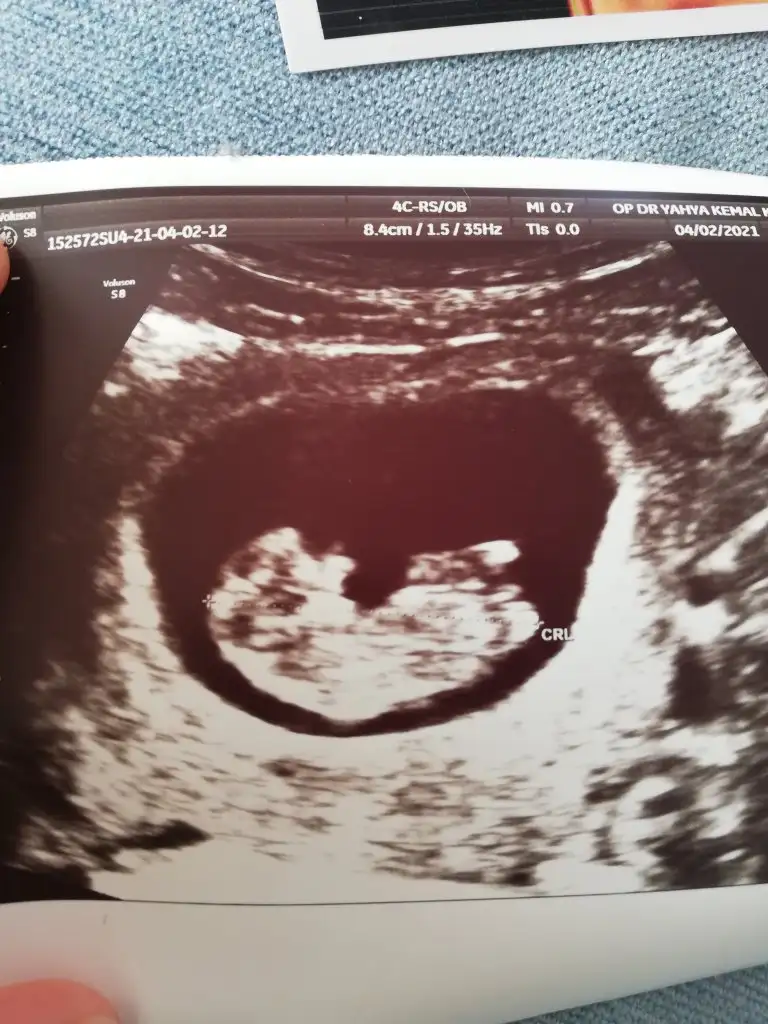

Kız görünüyor tekrar USG paylasinBana da tahmin edebilir misiniz rica etsem nuba göre 10+6 günlük :) Eki Görüntüle 2815755